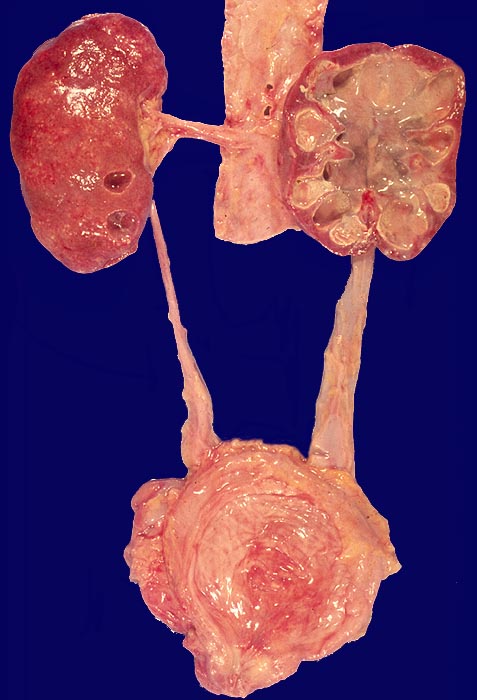

PathoPic – image database / PathoPic ID 1763 - Pyonephrose und Pyoureter, akute Pyelonephritis

Pyonephrose und Pyoureter, akute Pyelonephritis

Im Vergleich zur kontralateralen Seite ist der Ureter ausgeweitet. Auch das Nierenbecken ist dilatiert. Die Niere wird durch grosse rundliche Nekroseherde weitgehend zerstört.

Steinbedingter Ureterverschluss

Sekundäre Pyonephrose als Folge einer infizierten Hydronephrose.